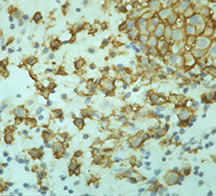

Microscopic Pathology

- Langerhans cell is diagnostic and clonal proliferation

- Nuclei show prominent nuclear groove (coffee-bean)

- Also composed of eosinophils and other inflammatory cells (non diagnostic component)

- Ratio of inflammatory cells to Langerhans cells varies

- Mitotic activity low

- Eosinophils dominate some areas forming diffuse sheets, excluding Langerhans cells

- Birbeck Granules: Electron Microscopy demonstrates granules that often take the form of a tennis raquet and form from complex invaginations of the cell membrane

- Vimentin, CD1 and S-100 positivity